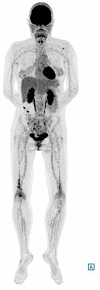

Erdheim-Chester disease (ECD) is a rare histiocytic disorder, recently recognized to be neoplastic. The clinical phenotype of the disease is extremely heterogeneous, and depends on the affected organs, with the most frequently reported manifestations being bone pain, diabetes insipidus and neurological disorders including ataxia. In this article, we report on a case of a 48-year-old woman, whose initial symptom of gait instability was isolated. This was associated with positional nystagmus with central features: nystagmus occurring without latency, clinically present with only mild symptoms, and resistant to repositioning maneuvers. The cerebral MRI showed bilateral intra-orbital retro-ocular mass lesions surrounding the optic nerves and T2 hyperintensities in the pons and middle cerebellar peduncles. A subsequent CT scan of the chest abdomen and pelvis found a left "hairy kidney", while 18 F-FDG PET-CT imaging disclosed symmetric 18F-FDG avidity predominant at the diametaphyseal half of both femurs. Percutaneous US-guided biopsy of perinephric infiltrates and the kidney showed infiltration by CD68(+), CD1a(-), Langerin(-), PS100(-) foamy histiocytes with BRAF V600E mutation. The combination of the different radiological abnormalities and the result of the biopsy confirmed the diagnosis of ECD. Many clinical and radiological descriptions are available in the literature, but few authors describe vestibulo-ocular abnormalities in patients with ECD. Here, we report on a case of ECD and provide a precise description of the instability related to central positional nystagmus, which led to the diagnosis of ECD.